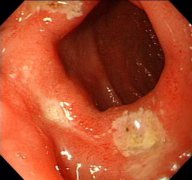

•   十二指腸炎怎么治療? 日期:2015-12-16 08:24:00 點(diǎn)擊:1616 好評(píng):38

十二指腸炎的治療概要: 十二指腸炎注意保持生活、工作、飲食的規(guī)律性。養(yǎng)成良好的飲食及生活習(xí)慣,避免服用刺激性食物。抑酸治療??咕委?。也可通過(guò)對(duì)癥治療。中醫(yī)學(xué)者認(rèn)為原發(fā)性...